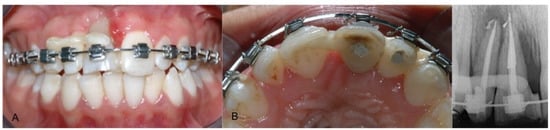

After 14 days, a transfer was used to take the impression. Temporary resin crowns were placed, and orthodontic treatment was completed. Follow-ups were scheduled and after 6 months, orthodontic brackets were removed. After 3 months, clinical and radiographic examinations were performed and showed good healing of soft tissues without infection. Subsequently, temporary crowns were replaced with the final crowns. Final crowns included cervical pink porcelain contours, in order to improve the frontal esthetics (Figure 4). A multilayer individual EVA mouthguard was delivered to be worn during sport activities. After 14 years, the implants were stable and bone volumes were maintained. Occlusion was stable and from an aesthetic point of view, final crowns were well integrated with neighboring teeth and gingival tissues.

Figure 4. (A) Provisional resin crown on the implant, (B) plaster model of provisional crown, (C) periapical X-ray control after provisional crown placement, (D) frontal view of definitive crown after 13 years, (E) lateral view and (F) periapical X-ray control after 13 years.